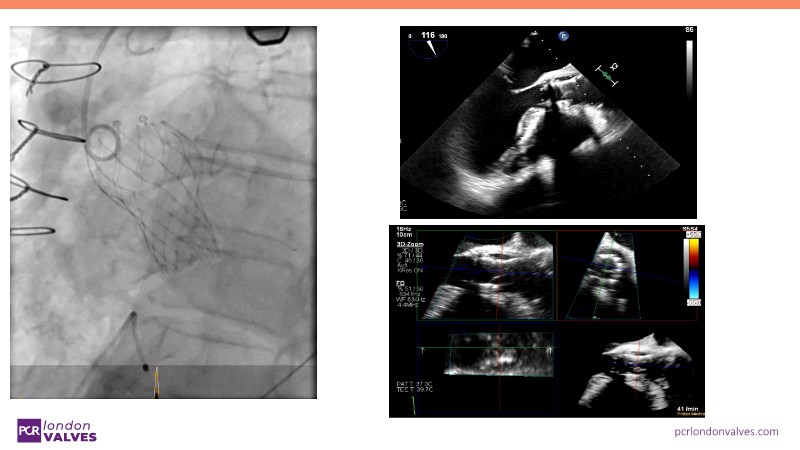

This session offers an in-depth review of complex TAVI cases, focusing on overcoming clinical challenges and achieving optimal outcomes with the Evolut FX+ device. Participants will learn about recent advances in TAVI indications for younger and asymptomatic patients, strategies for managing TAV in surgical aortic valve (SAV) patients including redo TAVI, and explore technological innovations designed to address complex anatomical scenarios.

- To discern the latest technological evolutions that enable the treatment of patients with complex anatomy